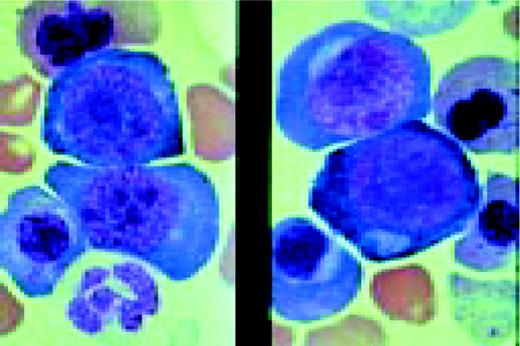

Prolymphocytic leukemia (PLL). This composite slide shows prolymphocytic leukemia (PLL) from two different patients. On the left is B cell PLL and on the right, T cell PLL. The B-PLL cells correspond to the classic description of Galton et al. (Br J Haematol 27:7, 1974): They are larger than CLL lymphocytes, have condensed chromatin, and have prominent large nucleoli. The T-PLL cells have a less conspicuous nucleolus, an irregular nuclear outline, and cytoplasmic blebs, as described by Matutes et al. (Blood 78:12, 1991). In many cases it may (FIX) be difficult to distinguish B-PLL from T-PLL cells on morphologic grounds alone, without performing additional immunophenotypic studies.FIG14